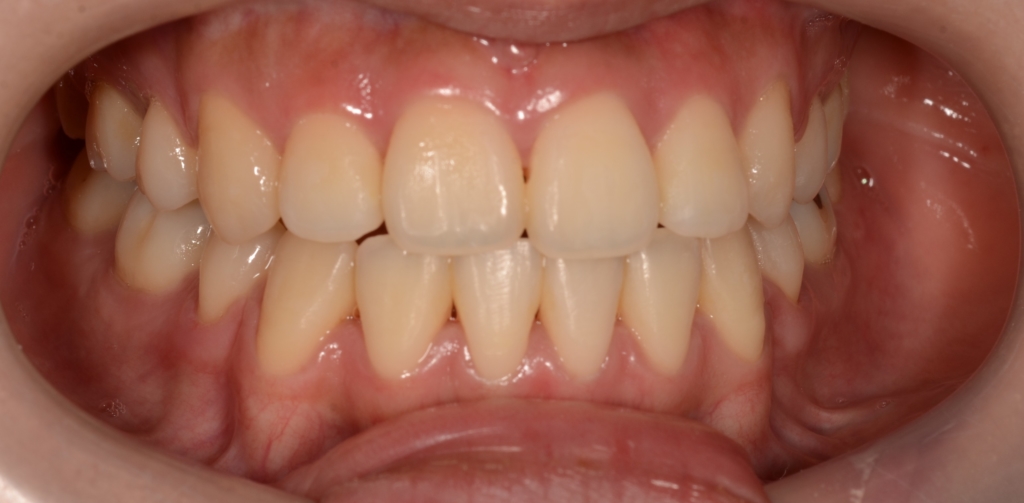

【After】

矯正治療の結果、Eラインに.しっかり収まりました。

口元の下口唇部を中心とした突出感(口ごぼ)は無くなり、狙い通りに口元をスッキリさせることが出来たように思います。 横顔も締まった良い感じに収まったように思えます。

それに伴い、お口を閉じる時の口元の緊張も消失して、楽にお口を閉じれるようになりました。

ついでに、歯並びの比較です

上段が矯正治療前、下段が矯正治療後